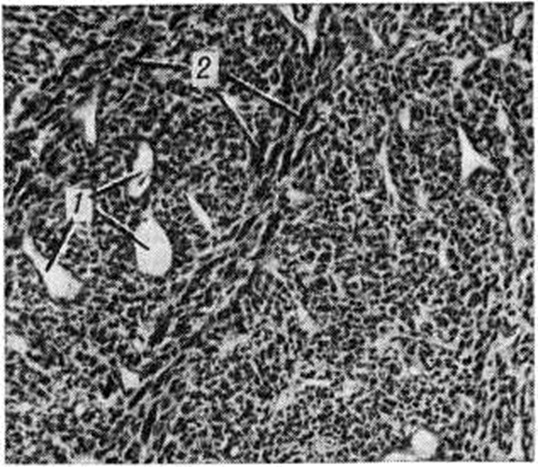

Рис. 2.

Микроскопическая картина недифференцированной гемангиоперицитомы: видны фигуры деления (указаны стрелками).

При микроскопическом исследовании наблюдается полиморфизм клеток; среди клеток преобладают веретенообразные формы, наблюдается обилие фигур деления (рисунок 2), прорастание клеток в просвет сосудов, инфильтрация окружающих тканей. Отличается агрессивным ростом, часто метастазирует (до 15% в регионарные лимфатических, узлы и до 50% в лёгкие) и рецидивирует (в 40—50% случаев).